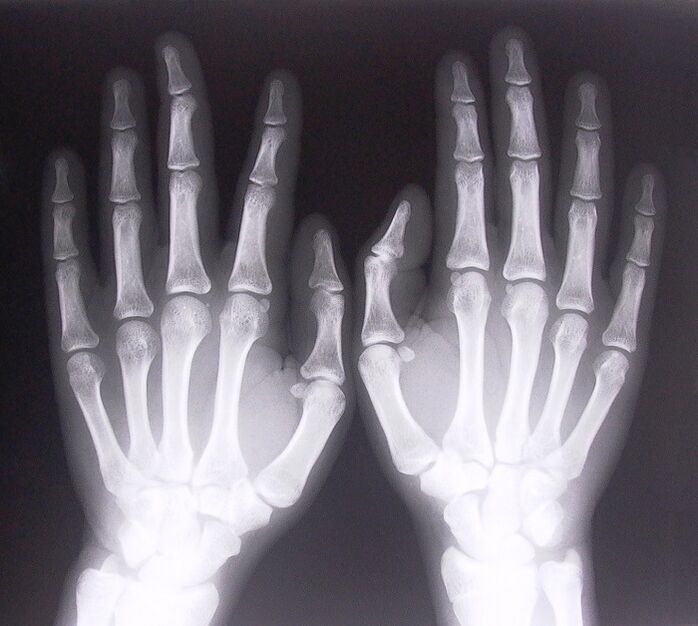

- Stenosing ligamentitis. Aron mahibal-an ang hinungdan sa sakit, kinahanglan nga moagi sa x-ray. Ang mga simtomas kasagaran: masakit nga paglihok sa kamot, pag-loop sa gikuyop nga palad. Usab, sa panahon sa extension, ang mga pag-klik sagad madungog.

- Pagkuha ug x-ray.